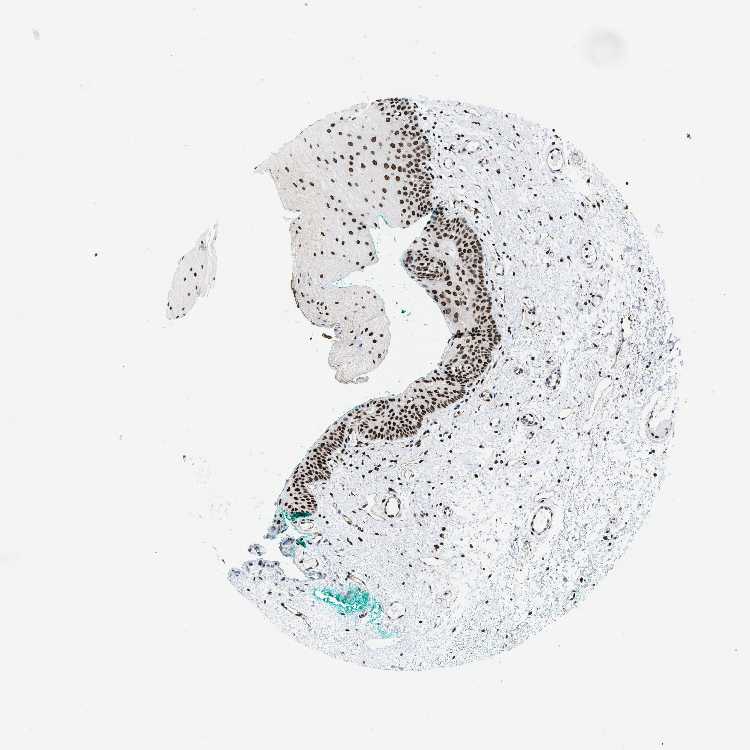

TISSUE PRIMARY DATA ORAL MUCOSA Show tissue menu

Oral mucosa

ORAL MUCOSA - Antibody stainingi

Antibody staining in the annotated cell types in the current human tissue is reported as not detected, low, medium, or high, based on conventional immunohistochemistry profiling in selected tissues. This score is based on the combination of the staining intensity and fraction of stained cells.

Each image is clickable and will lead to virtual microscopy that enables deeper exploration of all samples and also displays staining intensity scores, fraction scores and subcellular localization as well as patient and tissue information for each sample.

Antibody HPA016832Antibody HPA020076Antibody CAB001969

Squamous epithelial cells HighHighHigh